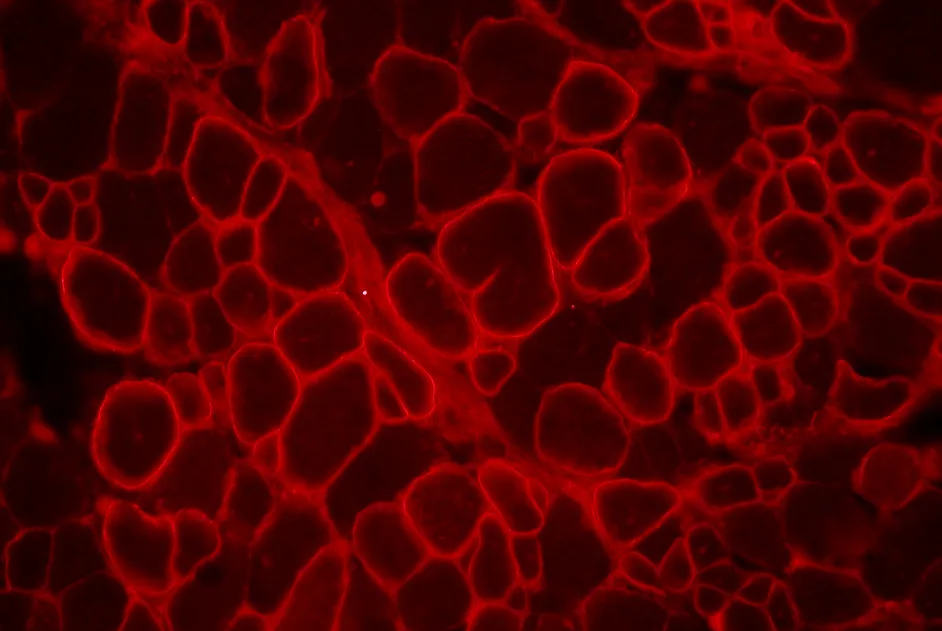

Dans un article publié en juin 2012, une équipe australienne a développé un poisson zèbre modèle de la myopathie myofibrillaire liée à la filamine C. Dans ce modèle, le gène de la filamine C est inhibé, entrainant une dissolution des fibres musculaire et la formation d’agrégats protéique, similaires à celles observées chez l’homme dans la myopathie myofibrillaire liée à la filamine C.